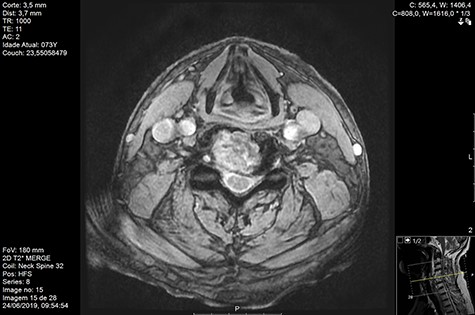

Computed tomography (CT) (Figs 1–3) and magnetic resonance imaging (MRI) (Figs 4–6) of the cervical spine were performed and revealed a lytic lesion involving most of C4, C5 and C6 vertebral bodies with bilateral extension to the posterior spinal elements of C4 and C5 and complete disruption of C4-C5 and C5-C6 intervertebral discs.

The Spinal Instability Neoplastic Score (SINS) [4, 6, 7] for assessing spinal instability from metastatic disease was used and the lesion was deemed unstable (SINS 13), with impending risk of increased neurological damage.